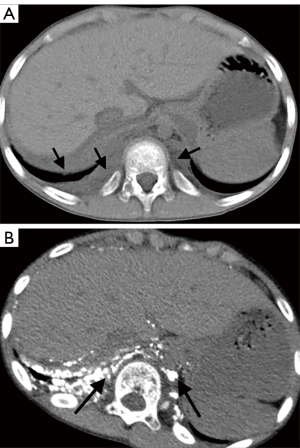

The involvement locations and incidence of bone lesions in 39 cases are detailed in Table 2. According to the morphology of bone lesions, these were divided into the following four types: (I) cystic changes (n=30; Figure 2), which showed single or multiple round-like cystic hypodense shadows in bone. The lesions had clear borders with or without sclerotic margins, and the maximum diameter was less than 5 cm. Marginal sclerotic margins (n=28), with one case showing iodized oil deposits within the lesion. (II) canal-like or honeycomb-like changes (n=34; Figure 3), which showed a tortuous, tubular distribution of hypointense shadow with clear margins and continuous at multiple levels above and below. The bone cortex was smooth or irregularly fractured in a worm-like pattern, while lesions were seen in 20 cases with iodized oil deposits. (III) Osteoporosis-like changes (n=16 cases; Figure 4), which showed a diffuse decrease in bone density and thinning of bone trabeculae. No lipiodol deposition was seen in any of the 16 cases in this group. (IV) Osteosclerosis-like changes (n=8; Figure 5), with two cases showing smooth thickening of the bone cortex, three cases showing increased density of osteophytes in the medullary cavity, three cases showing mixed presence, and five cases showing narrowing of the medullary cavity. Iodized oil deposition was not observed in any case.

A total of 11 cases underwent CT-enhanced scans of the chest and abdomen, and no enhancement was seen in any of the osseous lesions. The extraosseous lesions of 39 cases are shown in Table 3, Figures 6,7, and the abnormal distribution of lipiodol in different extraosseous areas in CTL are shown in Table 4, Figure 7D, and Figure 8.